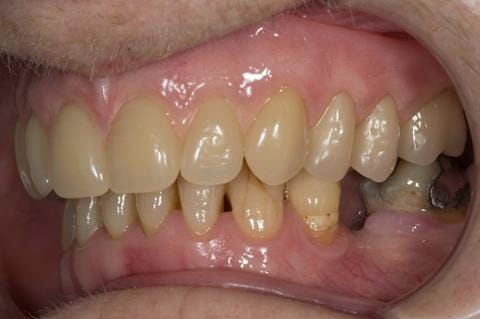

- Poorly fitting cobalt chromium based maxillary partial denture, which has been added to. This exhibited poor retention, stability and tissue fit (support). Unable to wear a new acrylic based denture.

- UR7 - occlusal amalgam. 10- 20% alveolar bone loss. Healthy periodontium with reduced attachment level. No mobility.

- Eight mandibular anterior teeth worn incisal edges from now extracted maxillary anterior crowns. Gingivitis - owing to inadequate oral hygiene.

- LL6 with large amalgam restoration - healthy periodontium.

- Bruxism.